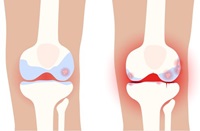

콘드로이친이 부족할 경우 연골은 보수성과 탄력을 잃는다고 합니다. 연골이 계속에서 닳게 되는 경우에는 뼈끼리 마찰이 생겨 부딪히게 되며 관절통이 진행되어 관절염 또한 쉽게 생길 수 있는데요. 콘드로이친 효능 중 가장 잘 알려진 관절통증을 완화시키는 역할을 통하여 얇아서 닳기 쉬운 연골의 마모를 방지해주는 일을하며 관절염의 통증을 개선하는데 도움이 됩니다.

콘드로이친이 연골을 재생시키고 보수성을 높이면서 무릎에 받을 수 있는 충격과 마찰을 흡수시키는 역할을 해 연골을 보호하는일을 하는데요. 실제 연구에서도 4개월간 꾸준히 콘드로이친 1200mg 정도를 섭취한 실험군에게서 관절과 연골의 통증이 43%이상 감소했다는 결과가 있습니다.

노화가 진행될수록 연골이 닳거나 관절 간격이 짧아지는데요. 이럴때 관절염 발생률이 점점 높아지는데요. 그러므로 생기는 통증으로 인하여 보행 능력도 점점 떨어집니다. 콘드로이친 효능 궁금하신 분들은 대부분 중장년층이라는 이야기가 많듯이 노화로 인하여 생기는 보행능력이나 관절통증에 대해 하루 콘드로이친 1200mg 보충을 권해드립니다. 간단한 섭취만으로도 보행 능력개선에 큰 도움이 된다고 합니다.